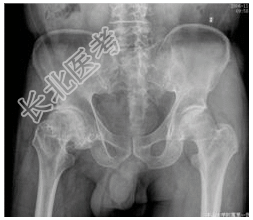

- [材料题] 患者男,53岁,右髋痛10余年,有酗酒史。查体:右髋压痛明显,4字试验阳性。行骨盆平片检查。

- 简答题1、患者的诊断及依据是什么?

- 简答题2、鉴别诊断是什么?